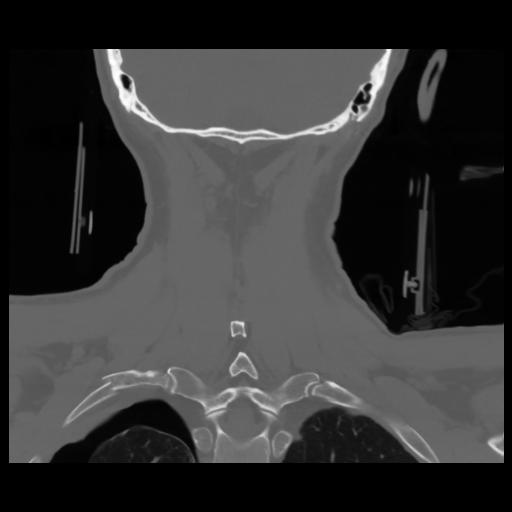

13 P.BLANDAS,,Coronal,2.000,P.BLANDAS,Coronal,